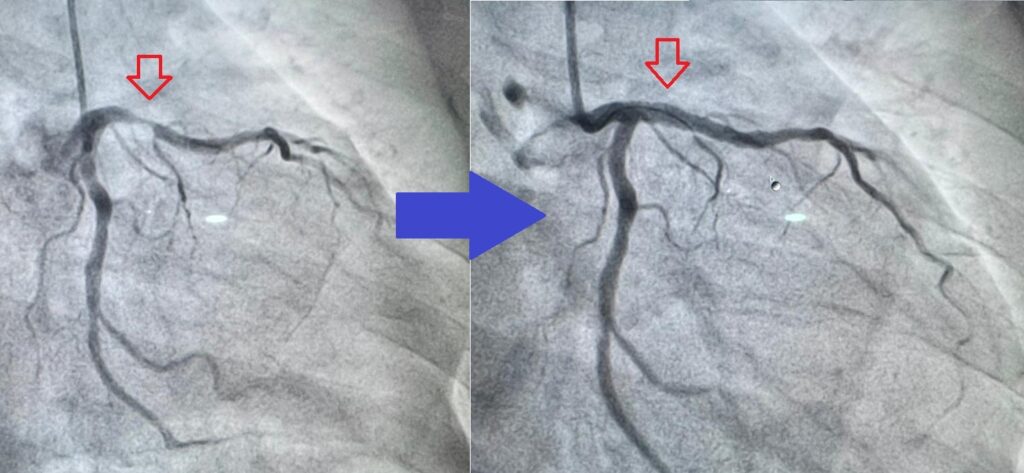

Setelah penilaian awal dan konfirmasi diagnosis, kami segera membawa pasien ke cath lab untuk melakukan Angioplasti Koroner. Prosedur ini bertujuan membuka pembuluh darah yang tersumbat menggunakan balon kecil, diikuti dengan pemasangan Stent Koroner untuk memastikan aliran darah tetap lancar.

Syukurlah, pembuluh darah yang tersumbat berhasil dibuka, dan aliran darah ke jantung kembali normal.